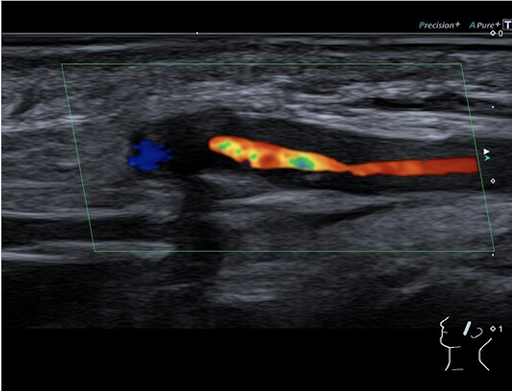

Farbkodierte Doppler Sonographie der linken Schläfe: Deutliche entzündliche Veränderung und Schwellung der Temporalarterienwand mit hochgradiger Stenosierung des Gefäßlumens.